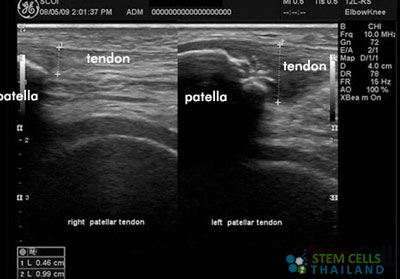

- PRP + Cells Therapy for Knees & Patellar Tendonitis – An injury that occurs mostly for athletes who do repetitive jumping and inflames and irritates their tendons. This happens mostly with people who plays baseball or are painters.